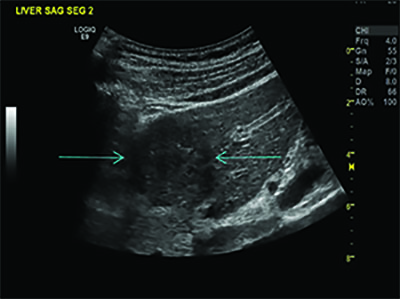

Dr. Forsberg’s colleague, John Eisenbrey, PhD, is in the early phase of a clinical trial studying UTMD on liver cancer patients undergoing radioembolization. The researchers introduced the microbubbles into the tumors and then destroyed them with acoustic waves, making the tumors more sensitive to the radiation. Follow-up imaging showed that of the seven patients who underwent UTMD, two experienced complete response to treatment and four had partial response. In contrast, only one of the four patients who did not undergo UTMD had a partial response and three had no response at all.